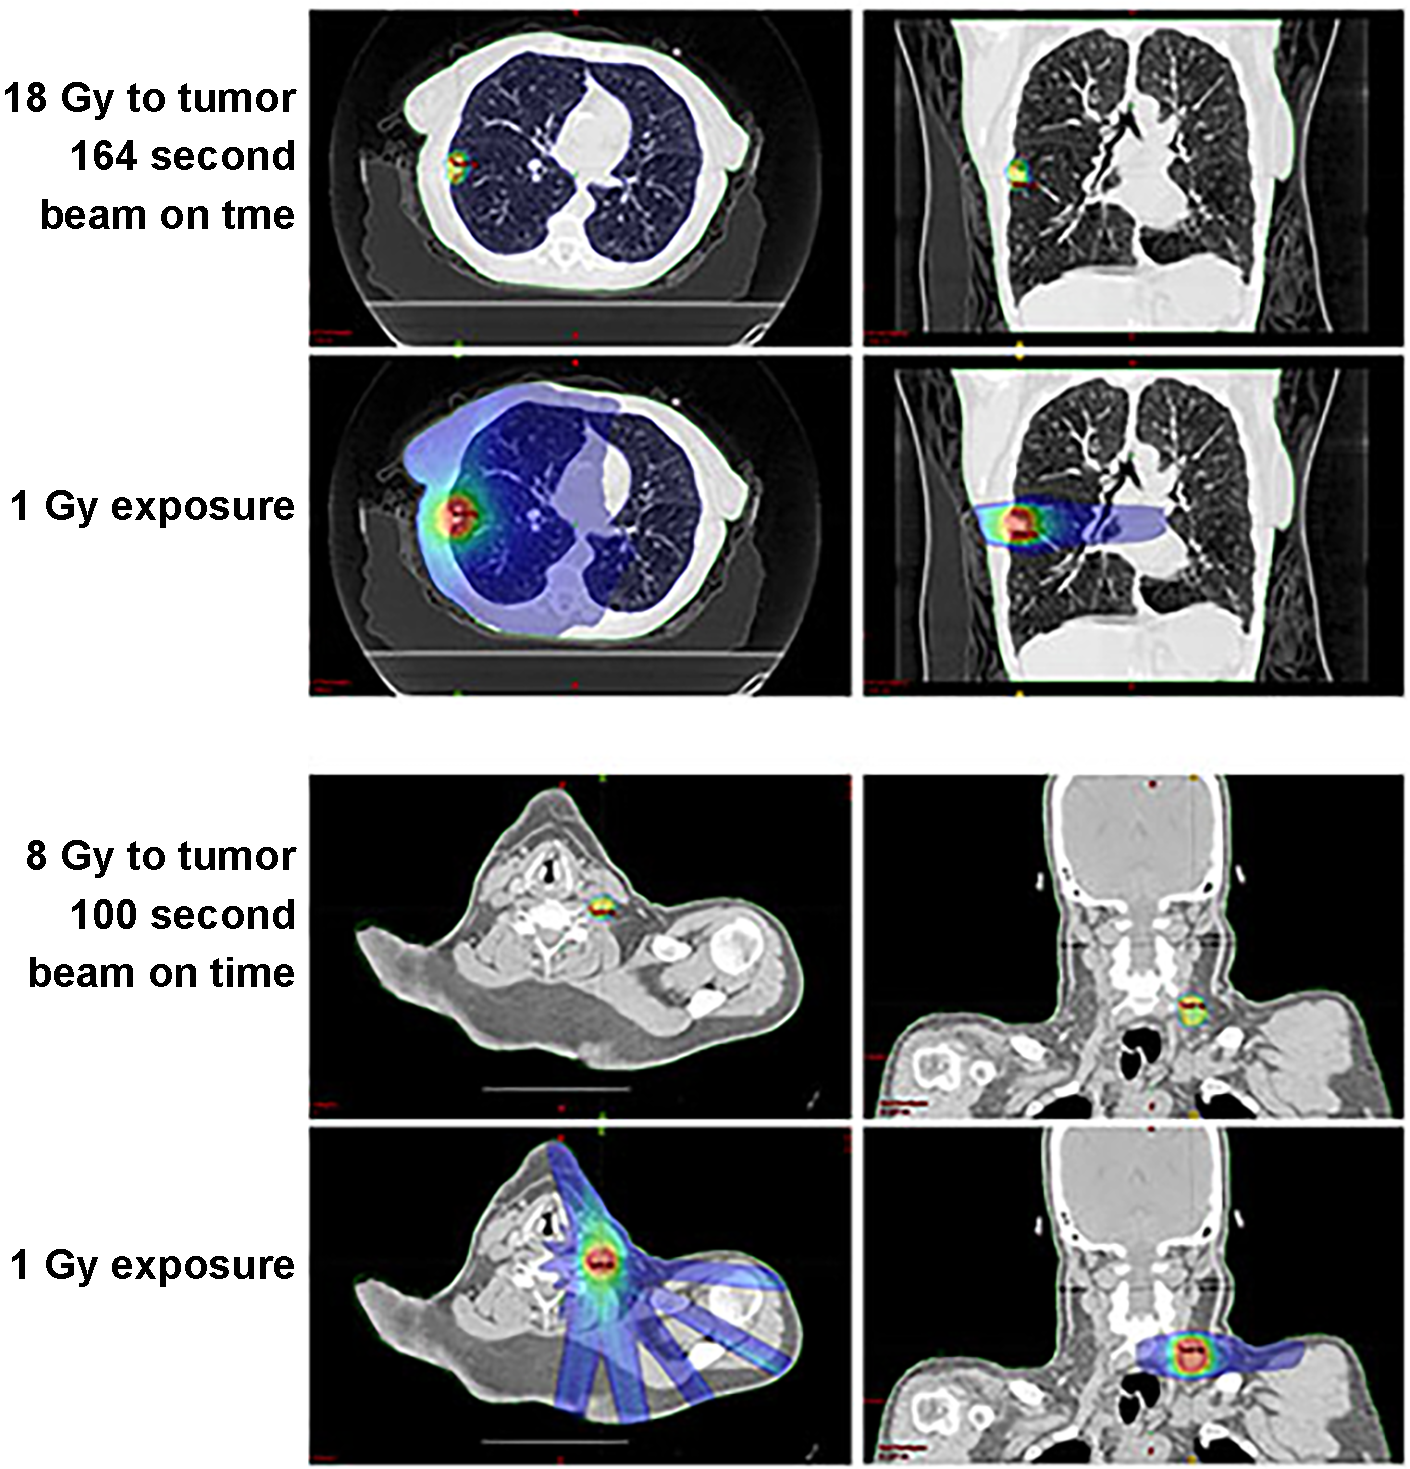

DNA Damage Signaling in Cancer Patients

ATM kinase activity is associated with ATM autophosphorylation on serine-1981, and antisera that recognize phosphorylated serine-1981 are the most sensitive marker of exposure to radiation and DNA damaging agents that has been identified. We developed a quantitative assay for ATM phosphorylation on serine-1981 and showed that ATM kinase-dependent DNA damage signaling is increased in the peripheral blood mononuclear cells (PBMCs) of patients treated with targeted radiation therapy. We showed that the circulation of blood through small tumors targeted with radiation for as little as 164 or 100 seconds was sufficient to induce DNA damage signaling in PBMCs throughout the patients body. We are interested in whether this is a predictive biomarker of response to radiation therapy and whether this changes the activity of immune cells in patients treated with radiation.